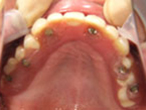

初診時

上下顎に数本の歯が残っていますが咬合支持がほとんどないために満足に食事もできない状態でした。また、下顎前歯部から臼歯部にかけて骨吸収が進行しており、上顎臼歯部にインプラント治療を行うためには骨造成が必要な状態です。

上顎

下顎